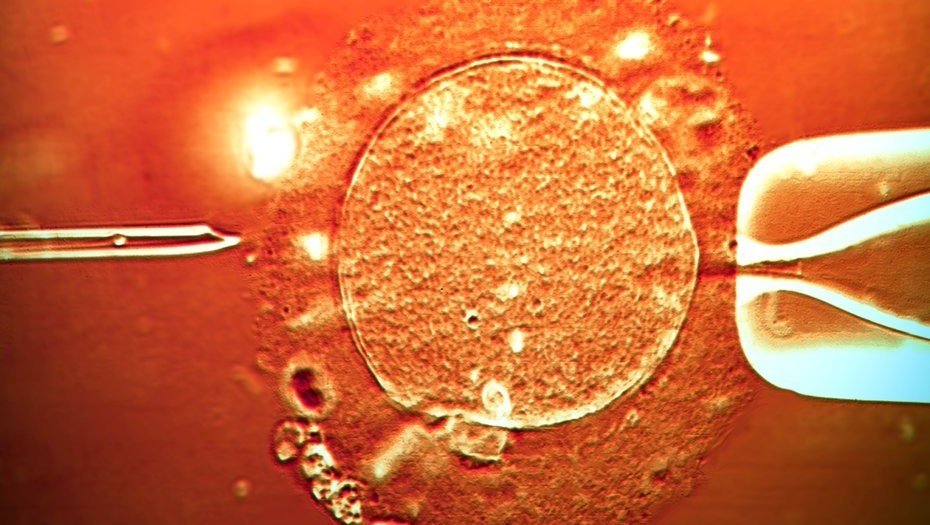

Fertilización asistida: a cinco años de la ley, se duplicó la cantidad de tratamientos

Ahora que las prepagas y obras sociales deben cubrirlos, hay 21 mil al año. Pero aún quedan trabas, según expertos.

A cinco años de la sanción de la ley 26.862, en la Argentina se duplicó el número de tratamientos de fertilidad. Actualmente se registran 21.000 ciclos al año de fertilización de alta complejidad, según la Sociedad Argentina de Medicina Reproductiva (SAMER), frente a los 10.000 previos a la sanción de la norma, en 2013. Sin embargo, expertos afirman que el país aún está muy lejos de alcanzar su potencial, estimado en 60.000 fertilizaciones anuales.